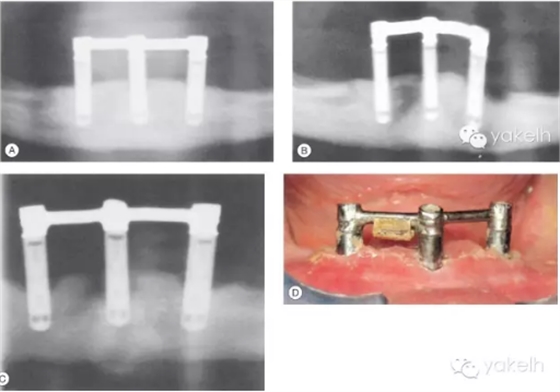

72歲女性患者,行下頜3顆種植體支持覆蓋義齒修復(fù)(圖.15A)。5年復(fù)查發(fā)現(xiàn)左側(cè)遠(yuǎn)中1顆種植體發(fā)生了種植體周圍炎(圖.15B)。在隨后的5年中,種植體周圍炎進(jìn)一步發(fā)展,在種植體周圍形成了彈坑樣的骨缺損(圖.15C)。

由于隨著患者年紀(jì)變大,身體越來越虛弱,而無法保持種植體周圍以及義齒下端的口腔衛(wèi)生,從而導(dǎo)致種植體周圍炎的易感性進(jìn)一步增加(圖.15D)。

對(duì)于種植體支持的覆蓋義齒而言,義齒內(nèi)陰性固位裝置的折斷也是經(jīng)常碰到的問題,盡管通過椅旁操作便可以進(jìn)行更換,但這仍然會(huì)給患者帶來麻煩。

圖.15 (A~C)這3張放射片間隔5年拍攝,顯示種植體周圍骨組織不斷喪失。 (D)口內(nèi)照顯示口腔衛(wèi)生差,種植體周圍軟組織存在炎癥。